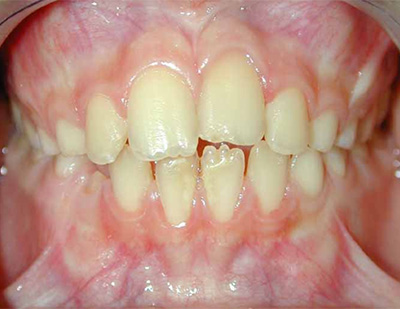

CASO CLÍNICO Paciente de diez años que acude a consulta de urgencias por haber sufrido un accidente deportivo 72 horas antes y como consecuencia del cual presentaba avulsión del incisivo central superior izquierdo 2.1.La familia guardó el incisivo en el congelador doméstico y acudió en esta situación a la clínica dental, pasadas 72 horas desde el traumatismo. Se exploró al paciente no apreciando fracturas óseas ni de otros dientes (Figura 1), se evaluó el diente avulsionado no apreciando fractura radicular ni coronal (Figura 2). Se exploró la zona alveolar no apreciando fracturas en las paredes del hueso alveolar. Después de obtener datos en la exploración clínica y debido a la edad del paciente se decidió realizarel reimplante.Tras la anestesia infiltrativa con lidocaina sin vasoconstrictor, selavó el diente avulsionado con suero fisiológico y se comprobó la adaptación del diente al alveolo.Se realizó el tratamiento de conductos en mano(Figura 3),y se eliminó el tejido pulparnecrótico y la posible contaminación bacteriana del mismo. La preparación quimio-mecánica se realizó con técnica manual, irrigando el conducto con hipoclorito sódico al 5% después de cada lima instrumentando hasta el número 30 con latécnica de step-bachy obturando con gutapercha y cemento Sealapex® (Kerr/Sybron, Romulus, MI EEUU).Posteriormente se realizó el reimplante del diente en el alveolo y la ferulización con alambre de ortodoncia y adherido con composite (Figura4).Se realizó una radiografía periapical de control (Figura5); citando al paciente para control en una semana. A las tres semanas se retiró la ferulización(Figura 6) y se realizó otra radiografía periapical (Figura7).Se realizaron controles clínicos al mes y seis meses, en los que no se apreció cambios en la evolución clínica. Tres años después a la exploración se apreció asimetría incisal atribuible a la detención dela erupción del 2.1, con limitación del crecimiento vertical(Figura8). Se observó los bordes incisales a distinta altura de los dientes 1.1 y 2.1, que son consecuencia de la anquilosis dental del 2.1 por lo que se aconsejóla erupción ortodóntica del 2.1 pero que el paciente no aceptó.El paciente permaneció sin síntomas inflamatorios. Diez años después de realizado el reimplante la radiografía periapical(Figura 9), muestra la reabsorción por sustitución y anquilosis dental como evolución del reimplante.En la exploración clínica el 2.1 presenta un retraso en la erupción, por la falta de crecimiento óseo vertical, con la consiguiente inclinación mesial del 1.1. El 2.1 presenta una restauración estética del borde incisal que fue realizada a los siete años del reimplantepara intentar mejorar la estética del paciente.A los quince años la radiografía periapical del reimplante (Figura 10), no muestra signos de inflamación activa, pero se puede observar la pérdida del contorno radicular en la zona media de la raíz en la cara distal; lo que indicaría la reabsorción radicular con aposición ósea posterior. DISCUSIÓN La educación de la población ante traumatismos dentales juega un papel muy importante a la hora de actuar en el lugar del accidente, especialmente en avulsiones dentales , lo que mejoraría el pronóstico de estos traumatismos. El tratamiento de un paciente que ha sufrido avulsión dental es largo y suele requerir un tratamiento multidisciplinario por lo que la colaboración del paciente y su familia es imprescindible , .En un reimplante tardío la evolución hacia la anquilosis es muy frecuente, siendo el factor más importante el tiempo en que el diente ha permanecido seco . En pacientes en crecimiento,la anquilosis, conlleva la falta de desarrollo óseo en sentido vertical, por lo queFillippi y cols. proponen que ante los primeros signos de anquilosis debemos recolocar el diente y recubrirlo con Emdogain, presentando algunos casos con buenos resultados en los que la anquilosis se detuvo. Tropeycols(6)aconsejan la sección de la corona y su extracción en los casos en los que aparezca anquilosis e infraoclusión de 2mm, dejando la raíz enterrada en el hueso para ser sustituida por éste y así poder favorecer el crecimiento vertical y posibilitar un mejor resultado estético definitivo.Ante la presencia de anquilosis en pacientes en crecimiento debemos actuar y no dejar el caso a su evolución natural puesto que el problema final será de más difícil solución(6). Es importante tener en cuenta que el autotransplante, generalmente con premolares, es una opción terapéutica de resultados predecibles , especialmente en pacientes en crecimiento que han perdido hueso y/o dientes en los que el reimplante no se pueda realizar o bien no vaya a tener resultados exitosos. El autotransplante mantiene el espacio dental, remodela el hueso alveolar y favorece el crecimiento óseo(10), por lo que funcional y estéticamentese puede obtener un resultado predecible. La sustitución de dientes perdidos por avulsión dental suele realizarse mediante la colocación de implantes dentales , lo que implica mantener al paciente durante varios años con soluciones provisionales hasta obtener el crecimiento definitivo del maxilar , alrededor de los 20 años de edad. En ocasiones a pesar de haber realizado tratamientos multidisciplinariosparamantener el espacio y los tejidos óseos y mucosos del diente perdido, a la hora de realizar el tratamiento definitivo con implantes dentales, no se puede obtener un buen contorno alveolar y altura ósea , ,lo que ocasiona un problema estético de difícil tratamiento. CONCLUSIÓN La avulsión dental tiene como consecuencia la probabilidad de la no supervivencia o la pérdida del ligamento periodontal. El paciente que está en crecimiento el pronóstico es desfavorable dado que las complicaciones son frecuentes. Se justifica el reimplante del caso por la edad del paciente y para posponer decisiones a una edad adulta. En el caso aquí presentado dada la evolución favorable no fue necesario el implante dental en el control realizado a los 15 años. La infraoclusiónpor anquilosis del diente reimplantado,se solucionó con restauración estética. BIBLIOGRAFÍA Bastone EB, Freer TJ, McNamara JR. Epidemiology of dental trauma: a review of the literature. Aust Dent J. 2000;45:2-9. Wriedt S, Martin M, Al-Nawas B, Wehrbein H. Long-term effects of traumatic injuries to incisors and periodontal tissuesduring childhood. J OrofacOrthop. 2010;71:318-29. Flores MT, Andersson L, Andreasen JO, Bakland LK, MalmgrenB, Barnett F et al. Guidelines for the management of traumatic dental injuries. II. Avulsions of permanent teeth.Dent Traumatol. 2007;23:130-6. .Andersson L, AndreasenJ O, Day P, Heithersay G, Trope M, Diangelis AJ, Kenny DJ, Sigurdsson A, Bourguignon C, Flores MT, Hicks ML, Lenzi AR, Malmgren B, MouleAJ,Tsukiboshi M. International Association of Dental Traumatology guidelines for the management of traumatic dental injuries: 2. Avulsion of permanent teeth.Dent Traumatol. 2012; 28: 88-96. Trope M. Avulsion of permanent teeth: theory to practice. Dent Traumatol. 2011;27:281-94. Hecova H, Tzigkounakis V, Merglova V, Netolicky J. A retrospective study of 889 injured permanent teeth. Dent Traumatol. 2010;26:466-75. MonaAl-Sane, Bourisly N,TaghreedAlmulla, Andersson L. Laypeoples preferred sources of healthinformation on the emergency management of tooth avulsión.Dent Traumatol. 2011; 27: 432-7. Maseng AL,Skaare AB. Management of a 9-year-old boy experiencing severe dental injury - a 21- year follow-up of three autotransplants: a case report. Dent Traumatol. 2011; 27: 468-72. DiAngelis A J and cols. International Association of Dent Traumatol guidelines for the management of traumatic dental injuries: 1. Fractures and luxations of permanent teeth. Dental Traumatol.2012; 28: 2-12. Savi A. Central incisor loss after delayed replantation following avulsion: a contemporary restorative and adjunctive orthodontic management approach. Dent Traumatol. 2012; 28: 161-165; Day PF, Gregg TA,Ashley P,Welbury RR, Cole BO, High AS, Duggal MS. Periodontal healing following avulsion and replantation of teeth: a multi-centre randomized controlled trial to compare two root canal medicaments.Dental Traumatol.2012; 28: 55-64. Fillippi A, Pohl Y, Von Arx T. Treatment of replacement resorption by intentional replantation, resection of the ankylosed sites, and Emdogain - results of a 6-year survey. Dent Traumatol. 2006;22:307-11. Andreasen JO, Schwarts O, Kofoed T, Daugaard-Jensen J. Transplantation of premolars as an approach for replacing avulsed teeth.Pediatr Dent. 2009;31:129-32. Anchieta RB, Rocha RP, Watanabe MU, De Almeida EO, Freitas-Junior AC, Martini AP, Barioni SRP. Recovering the function and esthetics of fractured teeth using several restorative cosmetic approaches. Three clinical cases.Dental Traumatol.2012; 28: 166-172. Zachrisson BU. Planning esthetic treatment after avulsionof maxillary incisors. J Am Dent Assoc. 2008;139:1484-90. Koh RU, Rudek I, Wang HL. Immediate implant placement: positives and negatives. Implant Dent. 2010;19:98-108. Jung RE, Pjetursson BE, Glauser R, Zembic A, Zwahlen M,Lang NP. A systematic review of the 5-year survival and complication rates of implant-supported single crowns. Clin Oral Implants Res.2008;19:119-30. Freitas Junior AC, Goiato MC, Pellizzer EP, Rocha EP,Almeida EO. Aesthetic approach in single immediate implantsupportedrestoration. J Craniofac Surg.2010;21:792-6. Figuras

Figura 8. Fotografía intraoral donde se aprecia el incisivo 2.1 a los tres años del reimplante.